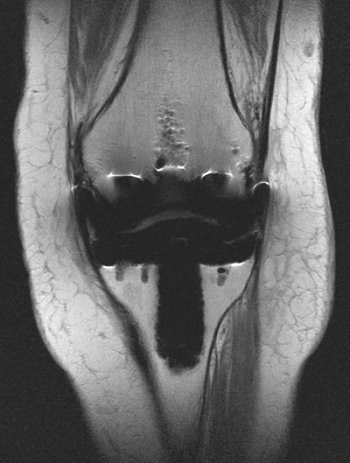

| MR scans of normal knee prosthesis. Above, coronal image (TSE: TR 3970, TE 54). Below, sagittal image (TSE: TR 4760, TE 54). All images courtesy of Dr. Kenneth Buckwalter. |

MRI has moderate spatial resolution, but, of course, excels at visualizing soft tissues. MRI offers indirect visualization of the cortical bone and hardware, Buckwalter stated. "Metal-friendly" MR sequences are fast spin echo and fast STIR. On the other hand, gradient echo, fat saturation, and spin echo are of little use for hardware-centered MR.